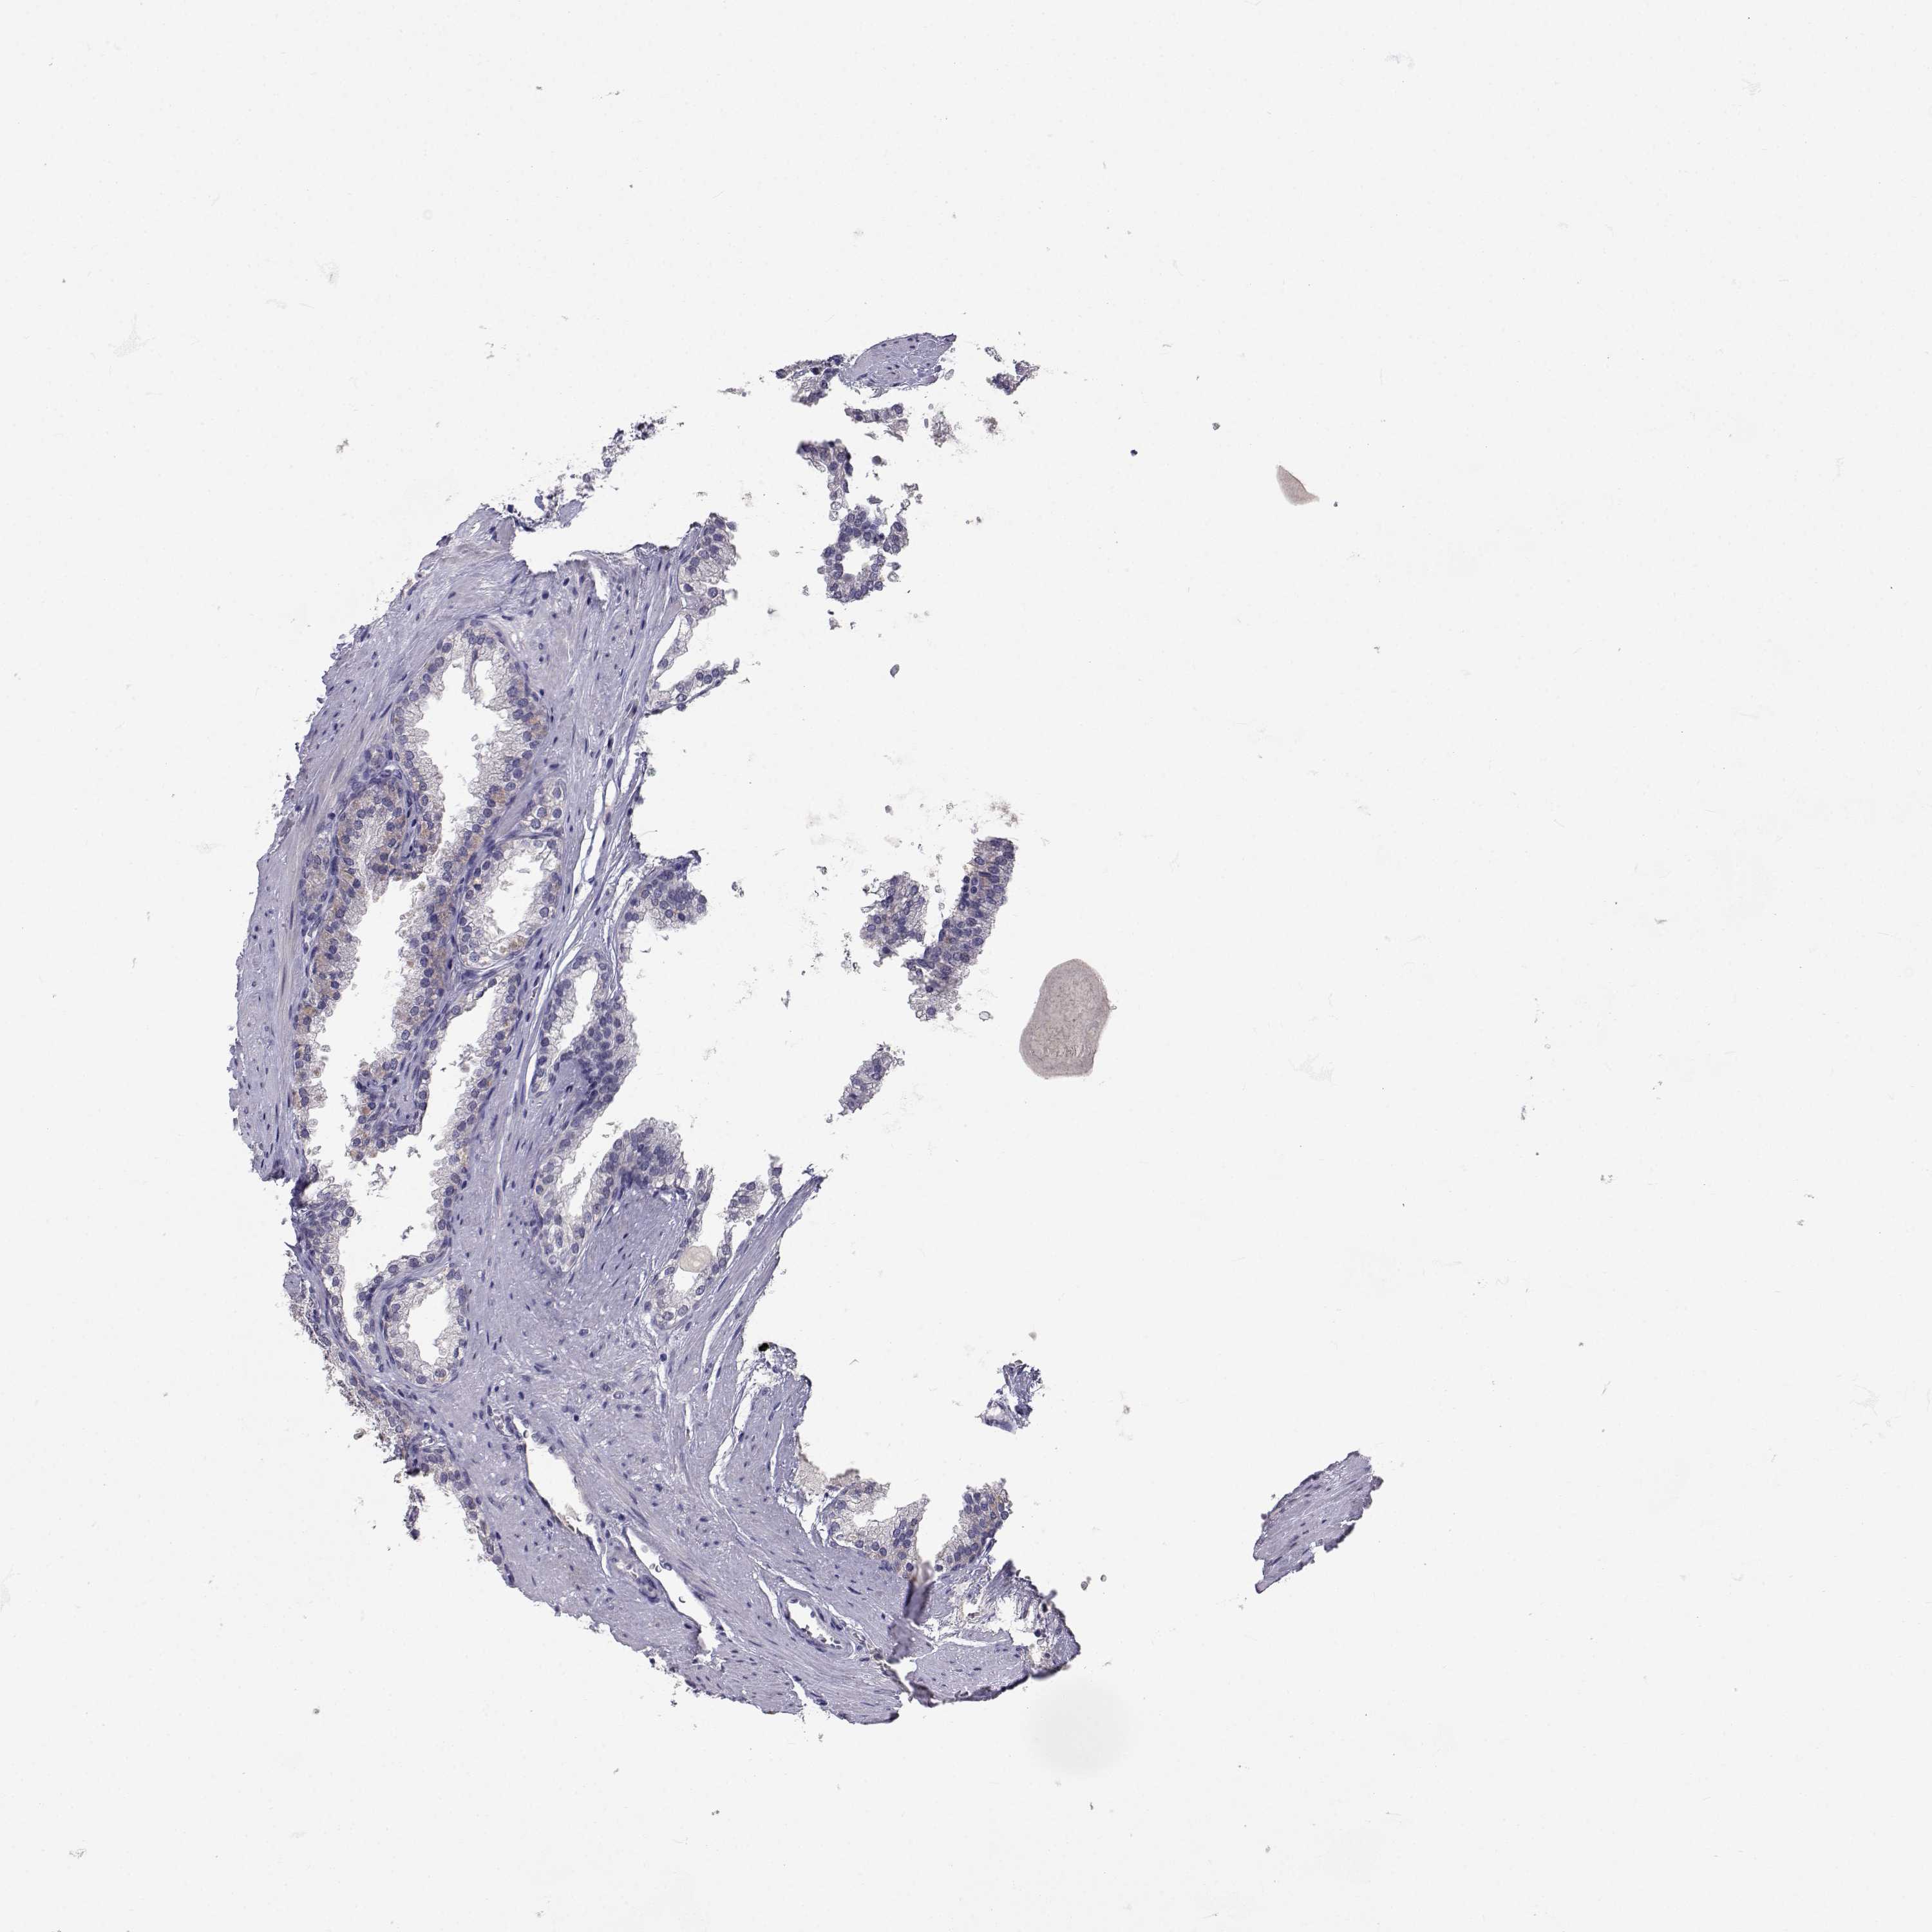

PROSTATE CANCER - Protein expressioni

A mouse-over function shows sample information and annotation data. Click on an image to view it in a full screen mode. Samples can be filtered based on level of antibody staining by selecting one or several of the following categories: high, medium, low and not detected. The assay and annotation is described here.

Antibody stainingi

Antibody staining in the annotated cell types in the current human tissue is reported as not detected, low, medium, or high, based on conventional immunohistochemistry profiling in selected tissues. This score is based on the combination of the staining intensity and fraction of stained cells.

Each image is clickable and will lead to virtual microscopy that enables deeper exploration of all samples and also displays staining intensity scores, fraction scores and subcellular localization as well as patient and tissue information for each sample.

Antibody CAB078172

Adenocarcinoma, High grade